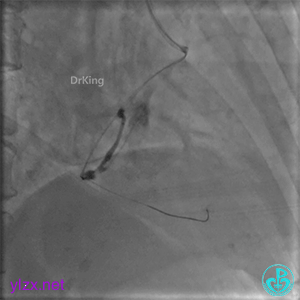

远段造影剂外渗在增加,怎么办?

微导管送入PL分支远段,取明胶海绵颗粒栓塞剂1ml通过微导管向远端血管推注栓塞远端血管。

封堵后造影,PL分支远端血流中断。